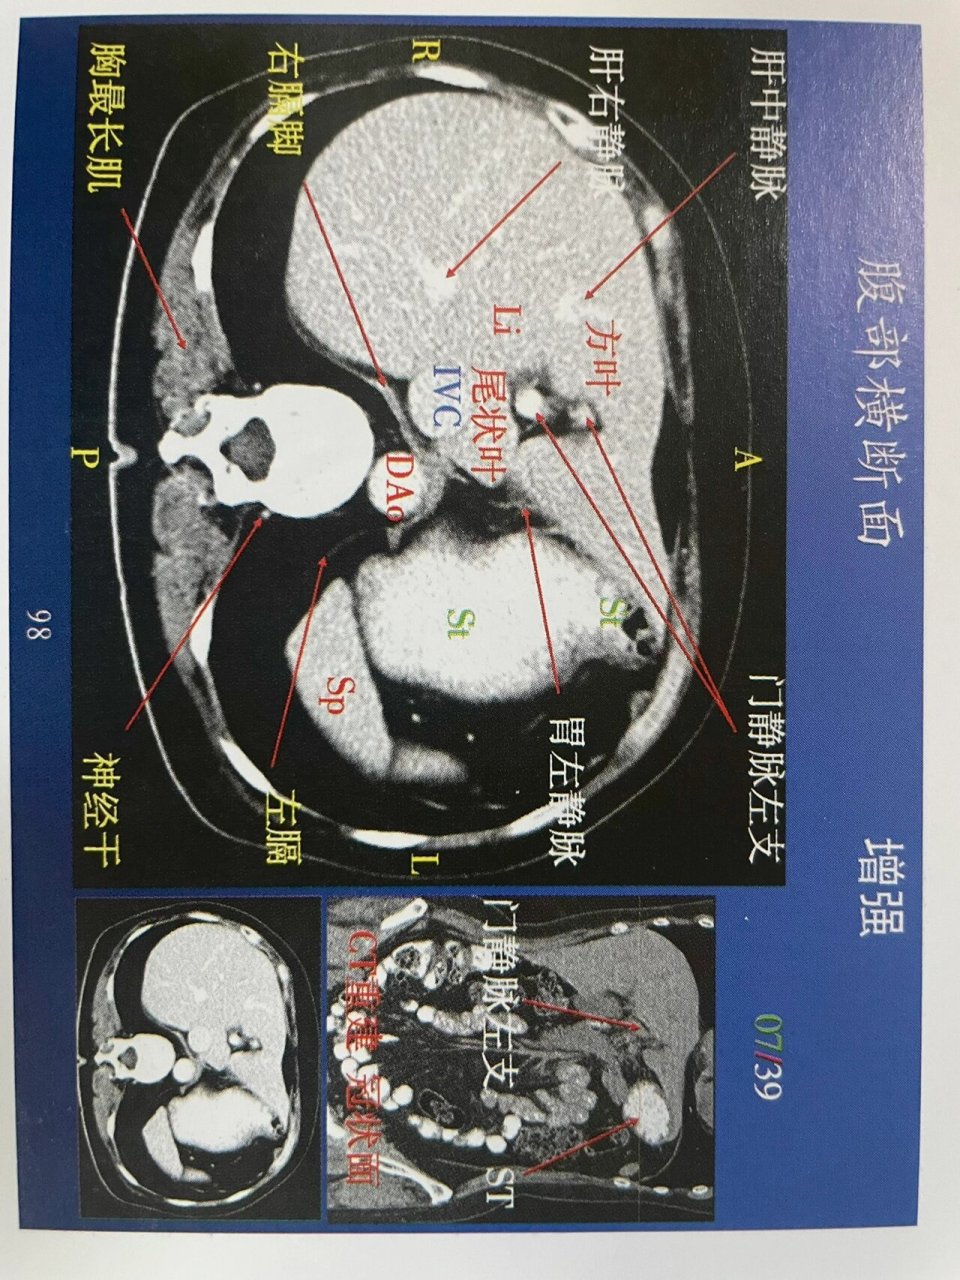

腹部第一组增强解剖!肝脏ct增强解剖!上腹部 肝脏详细横断面解剖图!